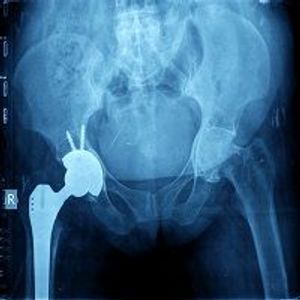

A study of patients undergoing total hip arthroplasty found that patients with psoriatic arthritis face no greater risk of poor outcomes than patients who get hip replacements because of osteoarthritis.